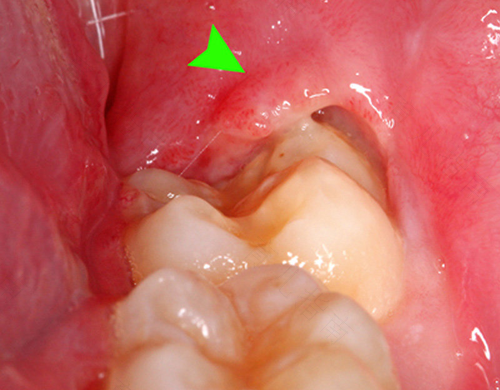

口腔没有护理好,很容易出现牙龈肿痛等现象。出现牙龈肿痛以后,如果没有及时治疗,就会影响食欲,也会导致睡眠不好。所以牙龈肿痛是不能忽视的,一定要及时进行治疗,那么就来了解一下牙龈肿牙齿痛怎么治疗?

如果平时没有注意口腔里的卫生,不刷牙漱口,就会导致牙齿内滋生细菌,从而引起的牙龈炎和水肿的现象。为了避免患有牙龈肿痛,早晚要记得刷牙,饭后也要用水漱口,保证口腔清洁,预防牙龈肿痛的发生。